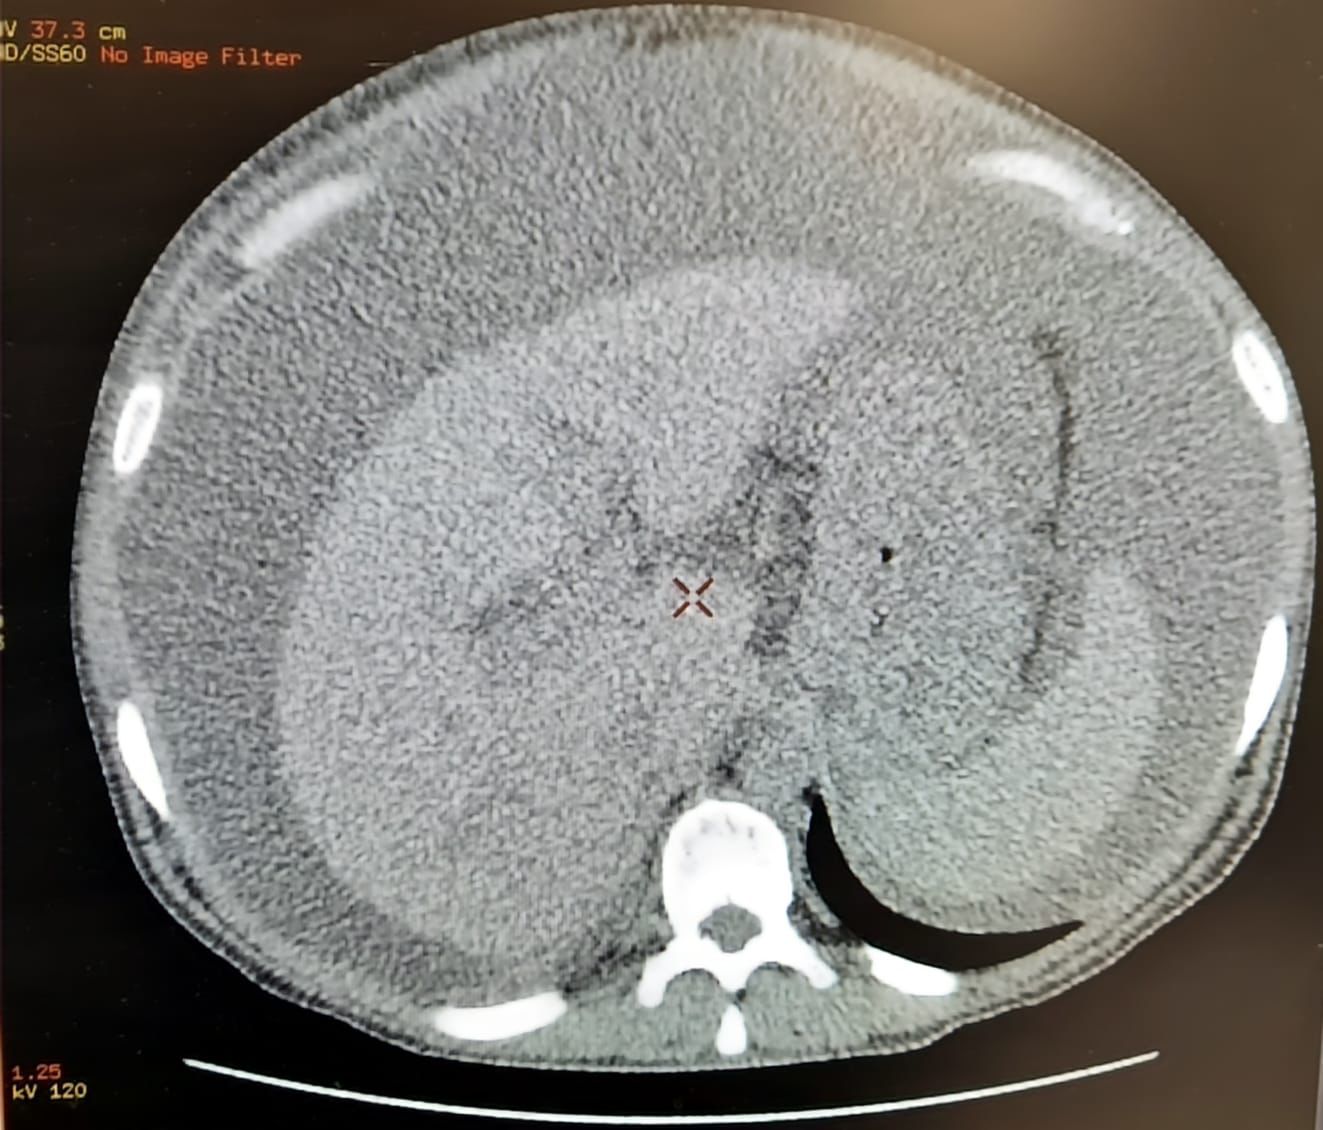

32-летнему мужчине сделали УЗИ и КТ брюшной полости. Уже на этапе диагностики врачи увидели, что практически все органы крайне сильно повреждены, особенно печень.

Развился массивный асцит: в брюшной полости скопилось около 10 литров свободной жидкости. Её придётся ещё не раз откачивать. Очень жаль, что молодой мужчина подорвал своё здоровье алкоголем. А ведь у него двое сыновей – их ещё нужно поднимать», - поделилась заведующая отделением лучевой диагностики Городской больницы №5

Сейчас пациент находится в терапевтическом отделении. Его состояние стабилизировалось, но цирроз на поздней стадии нее поддается лечению. Есть шанс только замедлить процесс заболевания. Это станет возможным при условии отказа от спиртного пациентом, а также своевременной медицинской помощи.